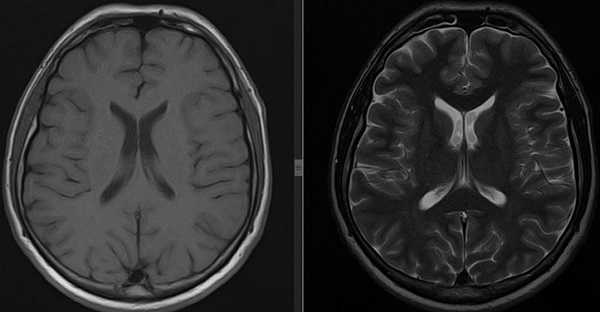

а — Т1-взвешенное изображение: ликвор гипоинтенсивный (темный)

б — Т2-взвешенное изображение: ликвор гиперинтенсивный (светлый)

У томографа предусмотрено множество режимов сканирования – Т 1, Т 2 взвешенные, ДВИ, FLAIR, STIR. Они отражают структуры статические либо в движении. Чем больше содержится молекул воды, тем темнее цвет ткани (для Т1 взвешенных снимков). И наоборот, чем плотнее ткань, тем светлее она на снимках. Так, если в сравнении с нормой в каком-то месте есть более темный очаг, это будет свидетельствовать об отеке или выходе жидкости из сосудистого русла. Светлое пятно говорит об уплотнении тканей – склеротический, опухолевый процесс. Для Т2 режима закономерность обратная.

КТ головного мозга МРТ головного мозга